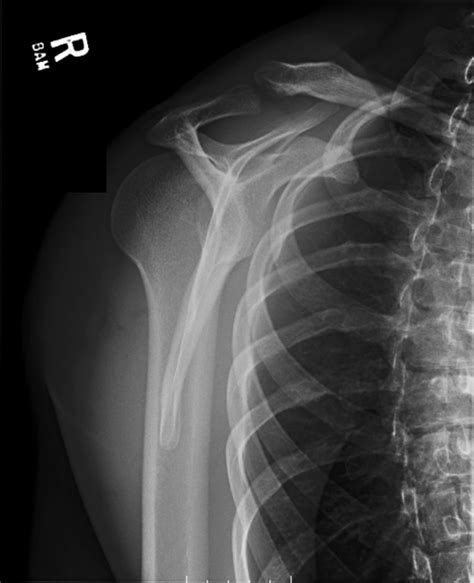

• Imaging Tests: X-rays are the primary imaging tool used to confirm the diagnosis. Additional tests such as CT scans or MRIs may be ordered to evaluate the extent of the injury and any associated damage to surrounding tissues.

Diagnosis of Posterior Shoulder Dislocation

Diagnosing posterior shoulder dislocation involves a combination of physical examination and imaging tests. The diagnostic process typically includes: